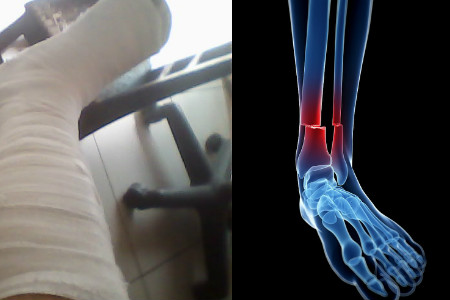

三、注意腿部保护

无论是在平时还是受伤期间,我们都要做好腿部的保护,这样才能防止腿部的受伤。腿骨折需要长时间的腿部固定和保护,所以我们要远离外界的一些碰撞,防止二次受伤。当然,没受伤的时候也要多提高警惕。